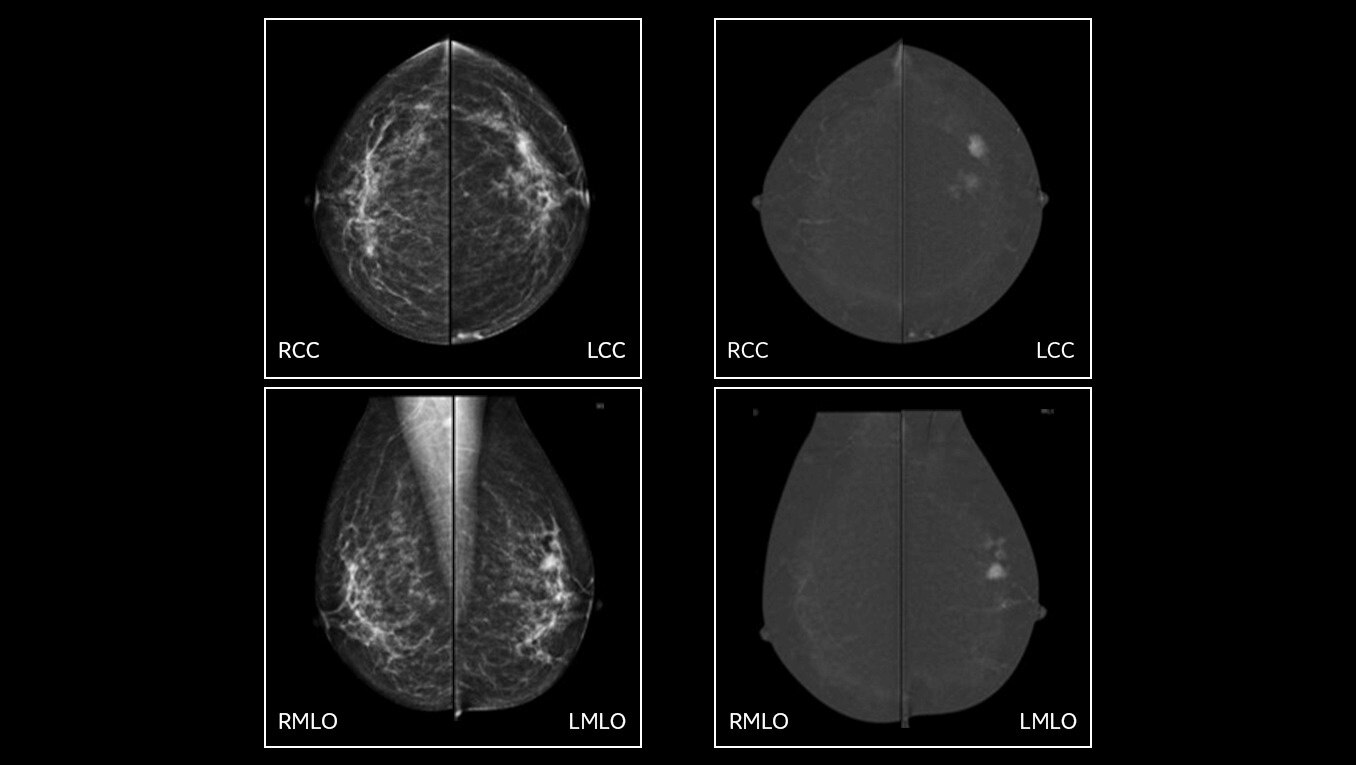

See differently, see clearly, see in contrast

Provide answers to your patients right away and help them avoid the agonizing wait that comes with an inconclusive exam. Don’t seek, see. Accelerate your ability to make a confident diagnosis.

• Helps reduce the masking effect of fibroglandular breast tissue and increases the tumour signal1.

• Contrast agent highlights areas of unusual blood flow.

• Find lesions that cannot be seen on routine mammography6,7,8.

• Provide high specificity for low false-positives1.